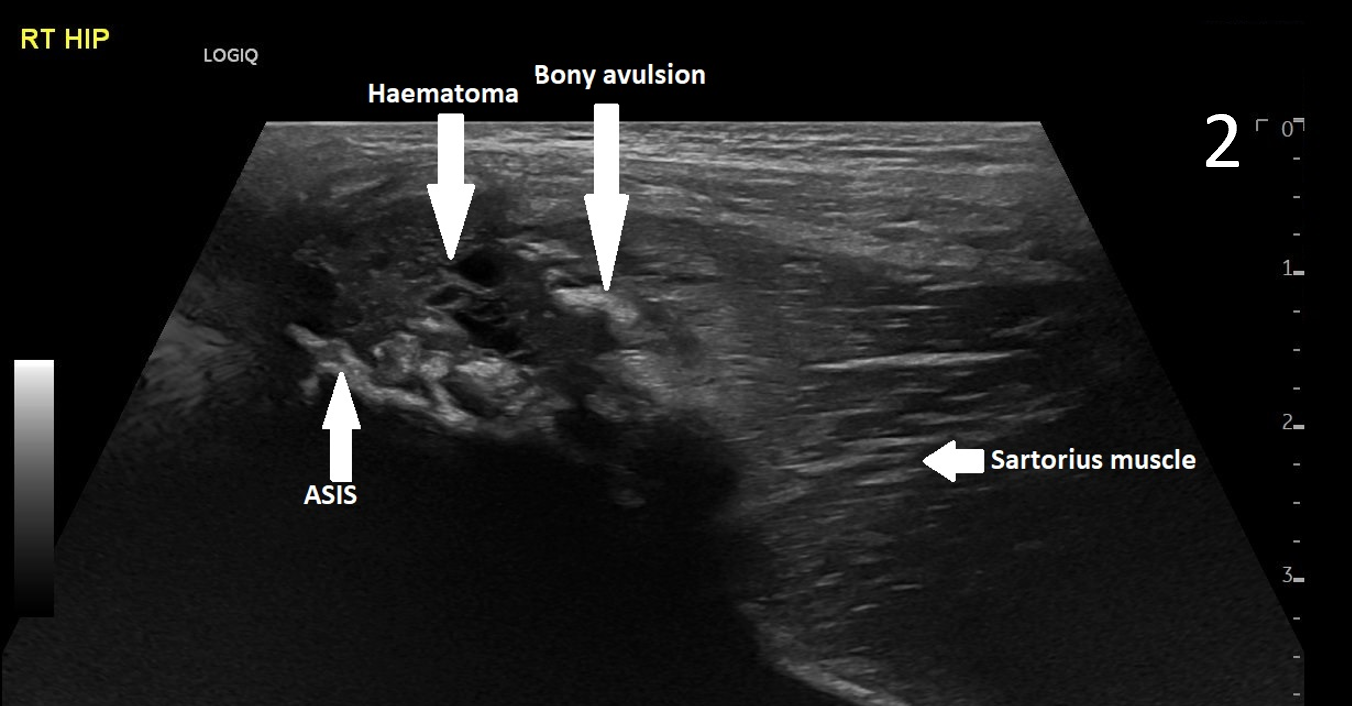

A 17-year-old male presented with severe pain in his right groin. He felt a ‘pop’ in his right groin whilst sprinting and was struggling to weight-bear. A radiograph excluded any bony abnormality (Figure 1) and an ultrasound scan showed no evidence of inguinal or femoral hernia.

The patient was focally tender in the right iliac fossa at the level of the anterior superior iliac spine (ASIS). At this site, there was muscle fibre disruption and a haematoma at the insertion of the sartorius tendon with minimal retraction (Figure 2). There was cortical irregularity at the ASIS and a bony fragment within the retracted tendon and also neovascularisation here on power Doppler (Figure 3). On comparison to the contralateral side, there was altered architecture of the sartorius muscle with a clear defect while the left side looked normal (Image 4). Ultrasound appearances in keeping with a sartorius tendon avulsion. This was treated conservatively with rest, analgesia and a return to normal activities after two months. Surgical interventions are uncommon and are reserved for when the fracture fragment has migrated more than 3cm.